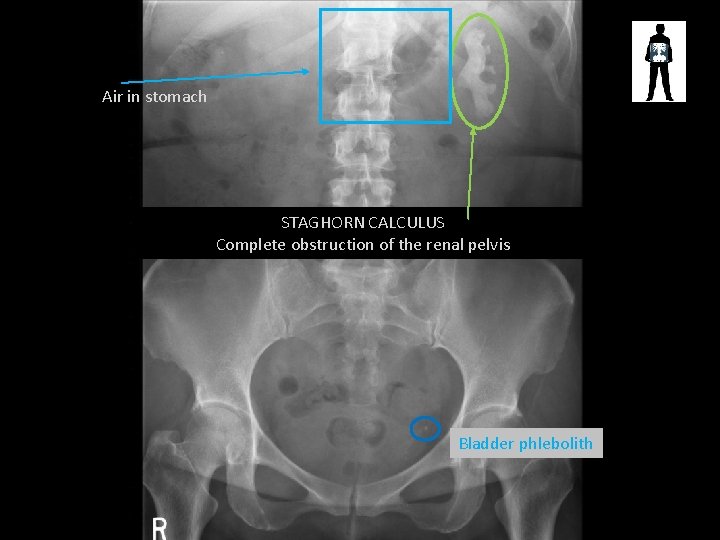

Air in stomach STAGHORN CALCULUS Complete obstruction of the renal pelvis Bladder phlebolith

RENAL CALCULUS

STONES! • Cause pain and obstruction of renal/biliary systems – Can be treated by surgical removal or laser fragmentation, lithotripsy or if small enough just monitored until they pass • Patients may undergo fluoroscopic procedures to treat these stones – ERCP – Retrograde Ureterogram – etc